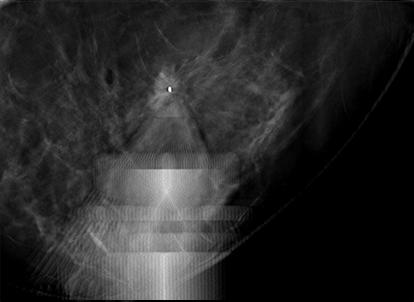

Superior imaging capability and a wider field of view.

With high quality 2D or tomosynthesis (3D™) imaging and a field of view that’s more than 6.5 times larger than older generations of prone biopsy systems,1 clinicians can visualize more tissue and pinpoint subtle lesions and faint calcifications that may not be visible on older systems. It also allows for easy software upgrade from 2D to 3D imaging at any time.

Featuring an automated tube-head motion, pre-programmed needle parameters and one-click targeting, the Affirm prone biopsy system is streamlined for efficiency. Its intuitive software and increased automation foster a faster, more efficient workflow, and fewer procedural steps help reduce the chance of manual errors.1

More than 95% of patients reported their Affirm prone biopsy procedure was faster, more comfortable and less painful than expected.3 The system is designed with patients’ physical and emotional comfort in mind. Direct view of the biopsy needle is eliminated, helping reduce patient stress, and clinicians can quickly identify, target and access lesions to help reduce time spent in compression.1